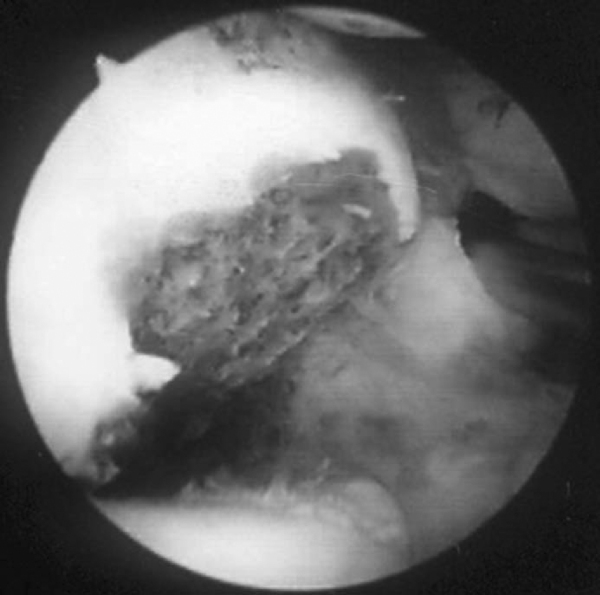

). This portal allows visualization of the entire posterior compartment as well as the medial and lateral gutters.[17] The blunt trocar is advanced toward the olecranon fossa through the triceps tendon and posterior joint capsule. The medial gutter is evaluated initially along with the olecranon fossa, and any loose bodies noted in either of these are removed. The arthroscope is then continued into the lateral compartment, and a soft spot portal is established. In most cases of osteochondritis, a relatively large posterolateral plica will be noted, along with quite a bit of synovitis in this lateral compartment (

Fig. 32-9

). The soft spot portal is located in the center of the triangular area bordered by the olecranon, the lateral epicondyle, and the radial head. This portal is also known as the direct lateral portal or midlateral portal (see

Fig. 32-4

). The blunt trocar passes through the anconeus muscle and the posterior capsule and into the joint. This inflammatory tissue is excised through a posterior soft spot portal. At this point, the 30-degree arthroscope is removed and a 70-degree arthroscope is substituted through the posterior central portal. Use of the 70-degree arthroscope allows complete evaluation of the osteochondritic lesion of the capitellum (

Figure 32-9 |